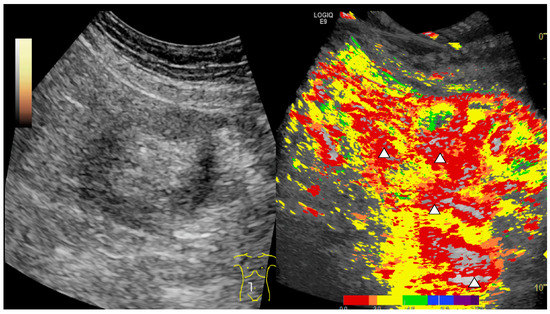

2.4. CEUS

2.5. Parametric Analysis

2.6. Ultrasound Image Analysis